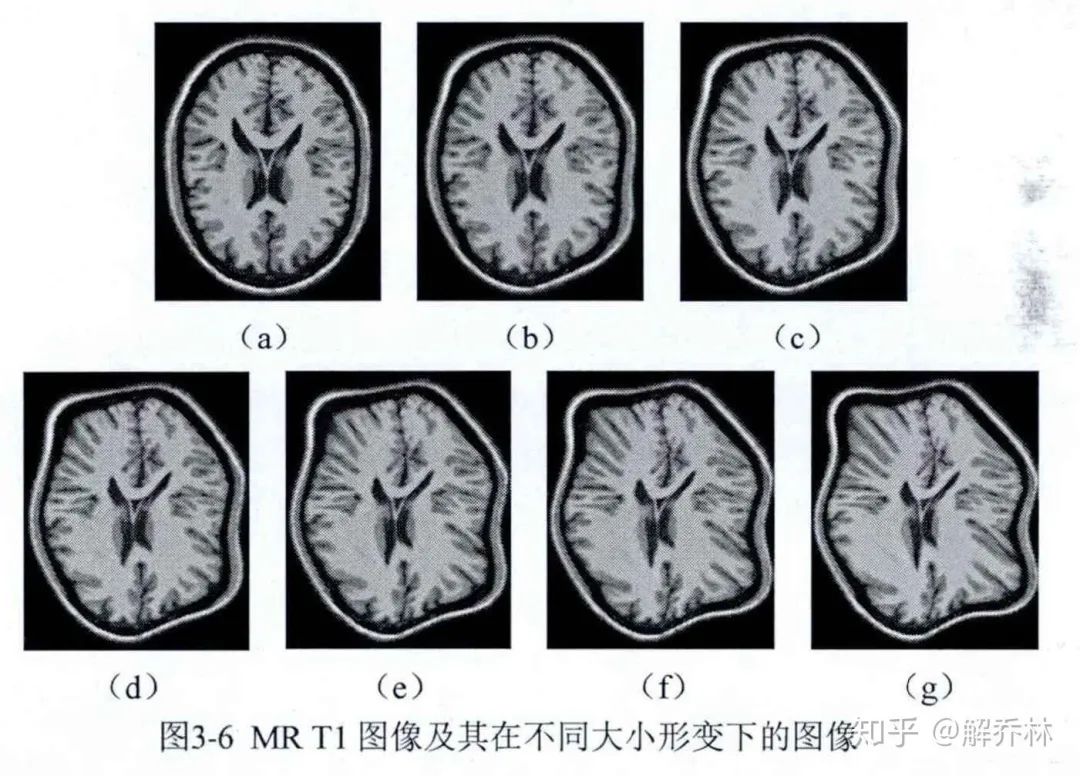

为了说明JAD的为可加性对图像配准的优化影响,我们利用JAD与互信息来配准MRT1的图像。

首先我们知道了金标准图,但是并不知道浮动图像,先用某种公式去将金标准变为不同浮动图像,然后再配准,然后再比较。

这个是我们的形变的公式,m代表形变量的大小,6组的形变系数出现六个图像,如下:

这个时候,我们把a作为参考图像,其他的作为浮动图像,利用JAD与MI对其进行配准,看一下其配准的效果,就可以知道谁更适合了。